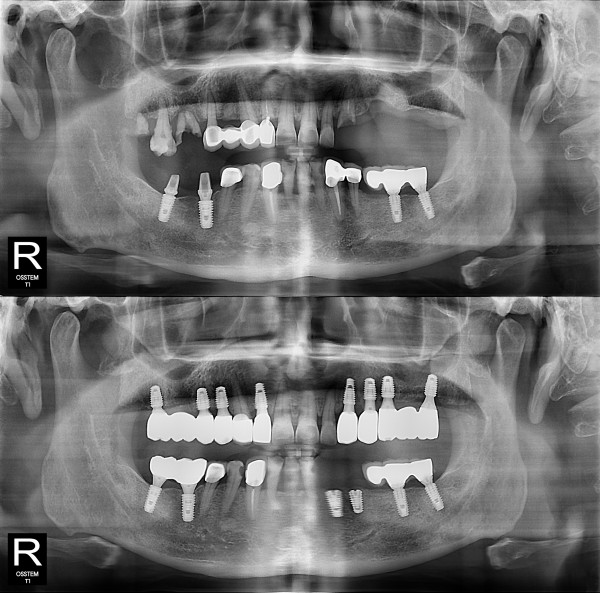

种植牙

全口种植牙